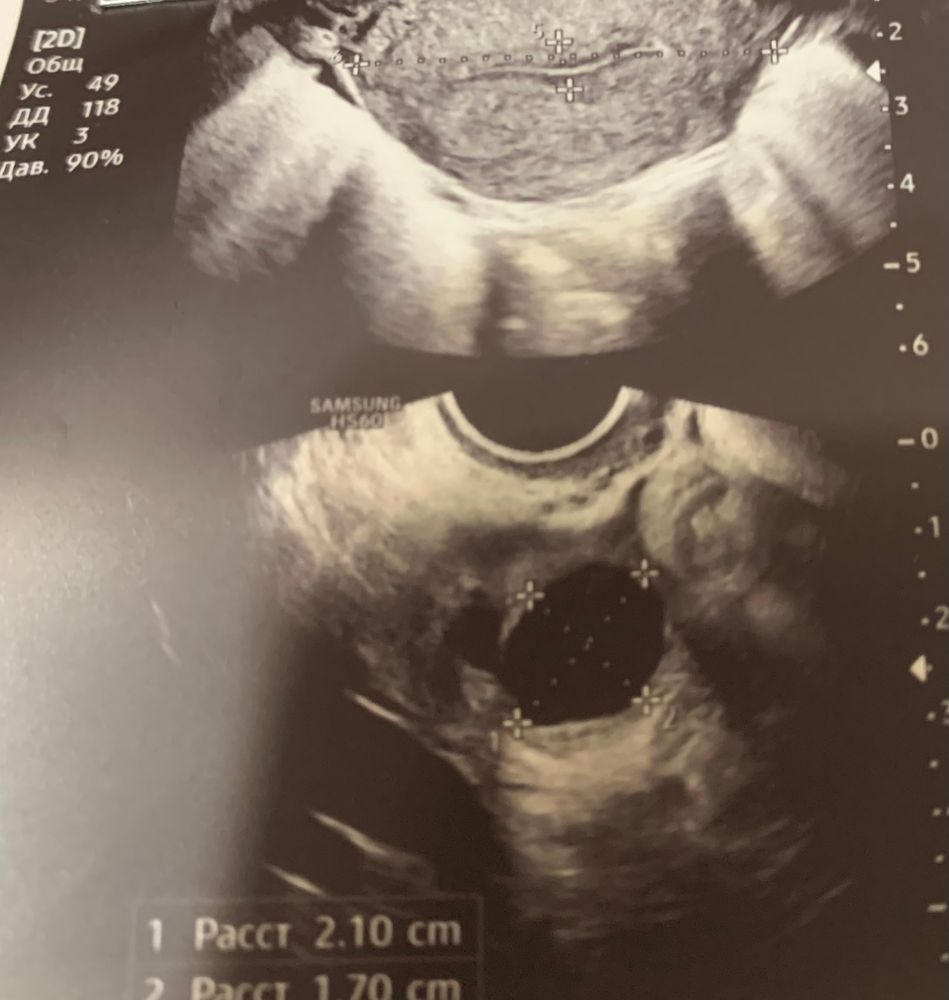

Была на узи на 8 день цикла. В левом яичнике, по словам врача, фолликулярная киста (около 20 мм). Эндометрий 5.4.

Могла ли узист спутать доминантный фолликул с кистой? Это единственный фолликул такой большой, остальные - мелкие, соответствуют 8 дню цикла.